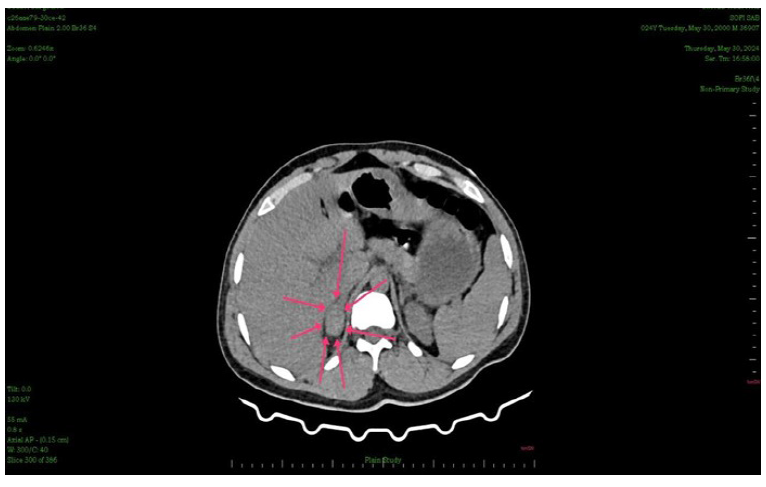

CT evaluation

CT scans were used to measure adrenal haematomas and classify them as irregular, oval, or circular. Other CT findings, including the enhanced area within the haematoma and associated injuries, were also evaluated (Figure 3 and 4).